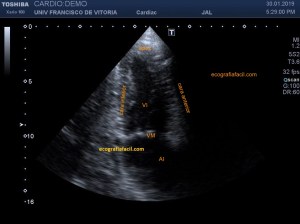

139. Ecocardiografía. Estudio Paraesternal Eje Largo.